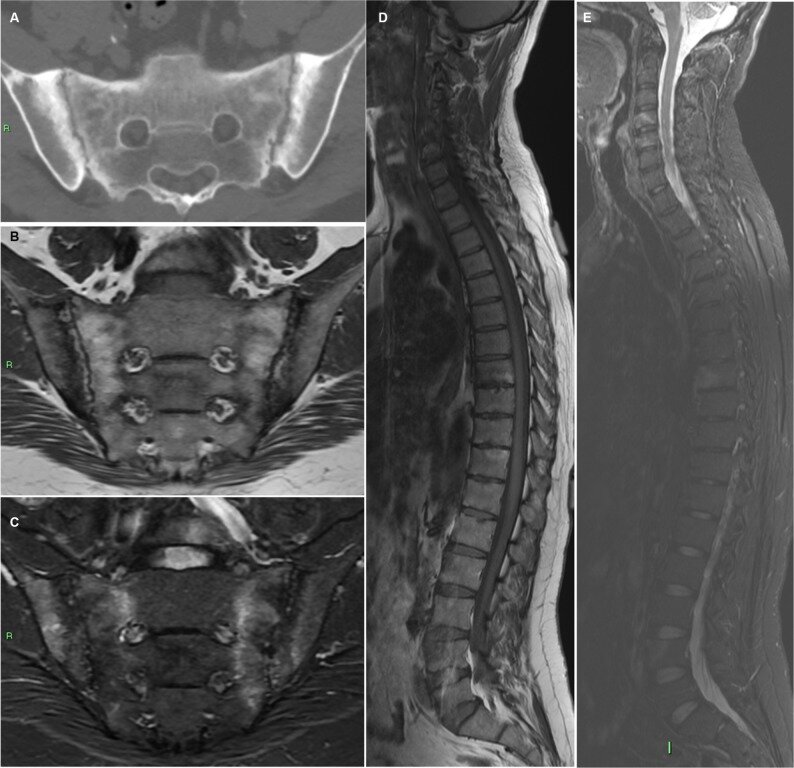

Компьютерная томография проводится в костном режиме высокого пространственного разрешения, преимущественно в аксиальной и сагиттальной реконструкциях. Основной диагностической задачей является выявление прямых признаков анкилозирующего спондилита, включая структурные изменения крестцово-подвздошных сочленений, позвоночных тел и фасеточных суставов. Исследование позволяет оценить степень костной перестройки, образования синдесмофитов и анкилозов на ранних и поздних стадиях болезни.

Компьютерная томография выявляет следующие признаки болезни Бехтерева:

Нарушение чёткости суставных щелей крестцово-подвздошных сочленений, визуализируемое в костном режиме при аксиальной реконструкции.

Субхондральная склерозированность и участки эрозий в зоне крестцово-подвздошных сочленений.

Полное сращение суставных поверхностей с формированием костного анкилоза.

Формирование тонких краевых синдесмофитов, распространяющихся вдоль передних и боковых поверхностей тел позвонков.

Кальцификация межпозвоночных дисков с формированием признака «бамбукового позвоночника».

Сужение межпозвоночных щелей и субхондральный склероз тел позвонков.

Симметричное сращение фасеточных суставов, особенно в грудном и поясничном отделах позвоночника.

Изменения осанки — усиление кифоза грудного отдела, снижение физиологического лордоза поясницы.

Костные мостики между телами позвонков, визуализируемые в сагиттальной проекции.